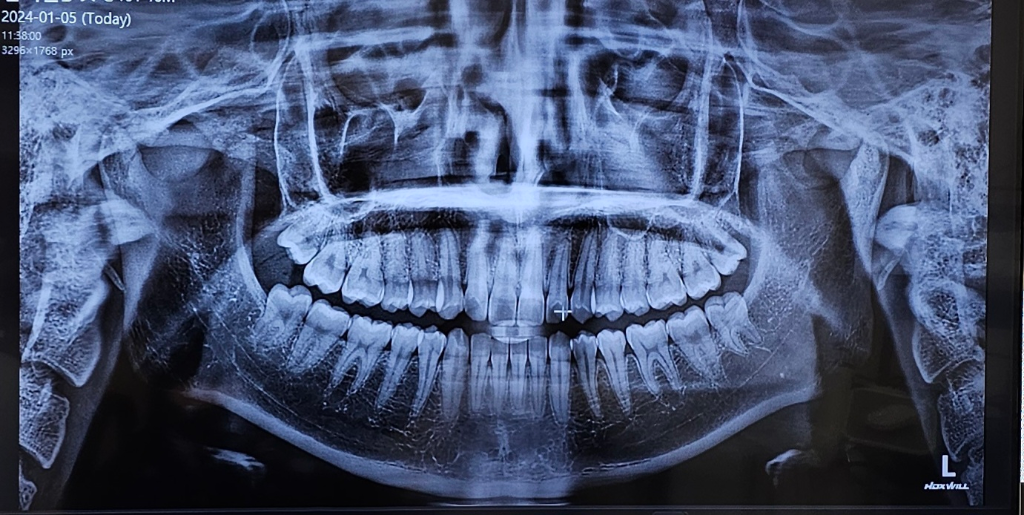

제 사랑니 위치 어떤가요? 예쁘게 난 편인가요?

어쨌든 잇몸에 반쯤 덮여있어서 자주 붓고 제가 느끼기에도 불편하긴 해서 뽑기로 하긴 했는데

엑스레이 보니까 궁금해져서요. 제일 바깥쪽에 있는 이빨 네 개가 사랑니 맞죠? 제 눈에는 곧게 난 것 같은데 어떤 편인가요?

뽑을 때 생니 뽑느라 막 으드득 소리나고 골 울리고 그런다는데 혹시 많이 아프게 나진 않았겠죠?ㅠㅠ